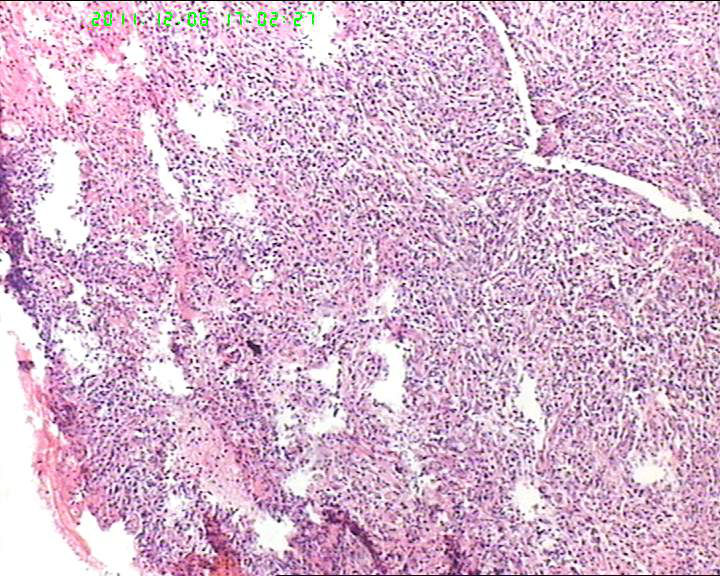

患者流脓涕1年,加重1月。左鼻腔息肉样增生物,质软,易出血。

送检灰白色绿豆大组织4块。

• 53岁女性患者,鼻腔肿物,中线恶网?韦格尔肉芽肿?图1

图1